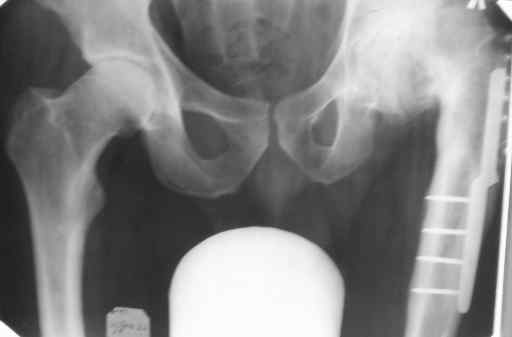

Уважаемые коллеги! Хотел-бы обсудить следующую ситуацию. Взял сегодня больного на операцию эндопротезирования. В августе удалил пластину ему пластину после корригирующей остеотомии в 1983г. Анализы все - норма.

Во время разреза мягких тканей, в подкожно-жировой клетчатке, обнаружил лигатуру в капсуле с гноем. Иссек, капсула крошечная - до 3 мм в диаметре. Больше ничего подозрительного не нашел. Эндопротез ставить побоялся. Сделали посев содержимого на флору и чувствительность к антибиотикам. Посевы пунктата из сустава (из трех точек), кровь и моча на стерильность трехкратно, иммунограмма. Вопрос, что еще сделать и сколько ждать? Юрий Алексеевич Булахтин

Извините, видимо я не слишком четко описал ситуацию. Больному пластина поставлена была в 1984г., в августе 2006г. я ее удалил. Удаление потребовало высверливания сломавшихся винтов поэтому с протезированием решили подождать. Сейчас, при осмотре рубца накануне операции, увидел точечную гиперемию, надавил на ткани вокруг - кожа лопнула и выделилась капля гноя.

Обработал кожу вокруг и пропунктировал сустав. После разрезом в два 2 см иссек гнойничок, оказавшийся осумкованной лигатурой. Анализы крови до и после норма. Вечерем, через 2 часа после иссечения температура однократно была 37, все остальное время - 36,6.